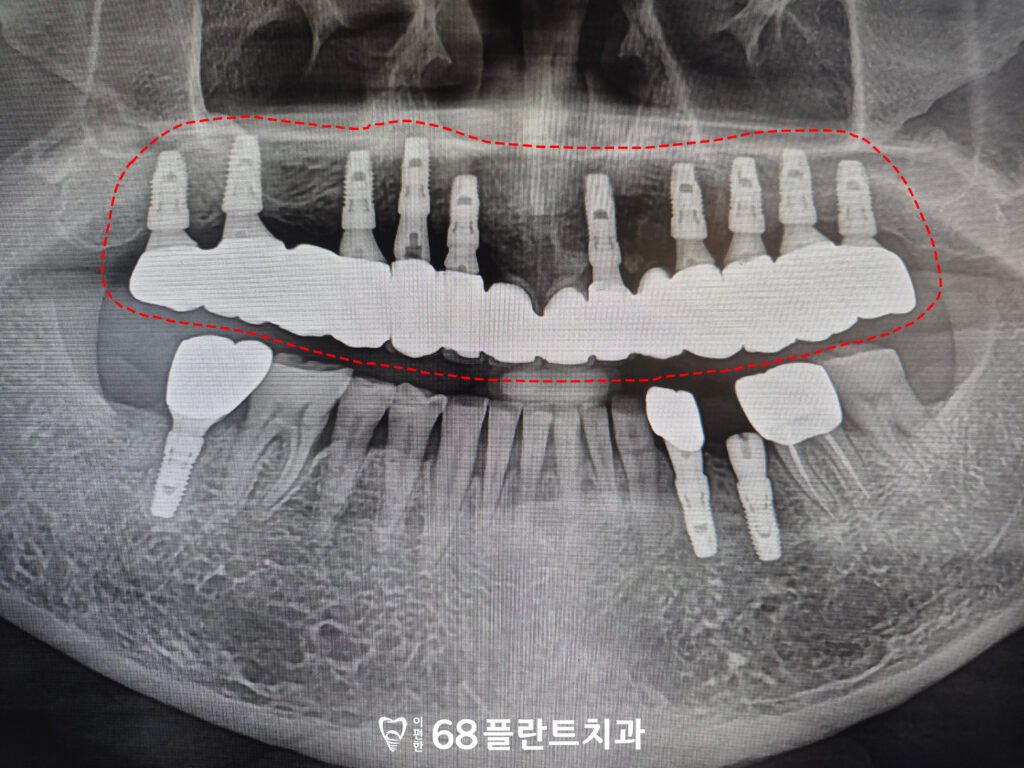

먼저 예후가 불량하다고 판단된

치아를 전체적으로 발치하고,

사전에 계획한 위치에 맞춰

임플란트를 식립하였습니다.

위쪽에 전체적으로

식립이 이루어졌기 때문에

교합의 균형과 식립 각도, 깊이를

더욱 정밀하게 고려해야 했습니다.

이후 치유가 안정적으로

진행된 것을 확인한 뒤에는

보철 제작을 위한 인상 채득 후

위,아래 관계를 정밀하게 분석하여

전체적인 저작 균형을 맞추는 데

중점을 두었습니다.

이후 제작된 보철물을 시적해 보며

적합도와 교합, 심미적인 부분까지 점검한 뒤

최종적으로 연결하여

기능적·심미적 회복을

마무리하였습니다.

그리고 아래쪽 역시 치아를 발치한 후

치료 계획에 따라

이후 치유 기간을 거치고

임플란트가 잇몸뼈에 잘 결합되어

보철 작업을 진행하였습니다.

위쪽 임플란트 보철에 맞춰

아래쪽 보철 역시 교합 관계를

세밀하게 조정하며 제작하였습니다.

최종 보철을 연결한 뒤에도

저작 시 불편감이나 이물감이 없는지 점검하였으며,

전체적인 교합 안정성을 확인한 후

치료를 마무리하였습니다.